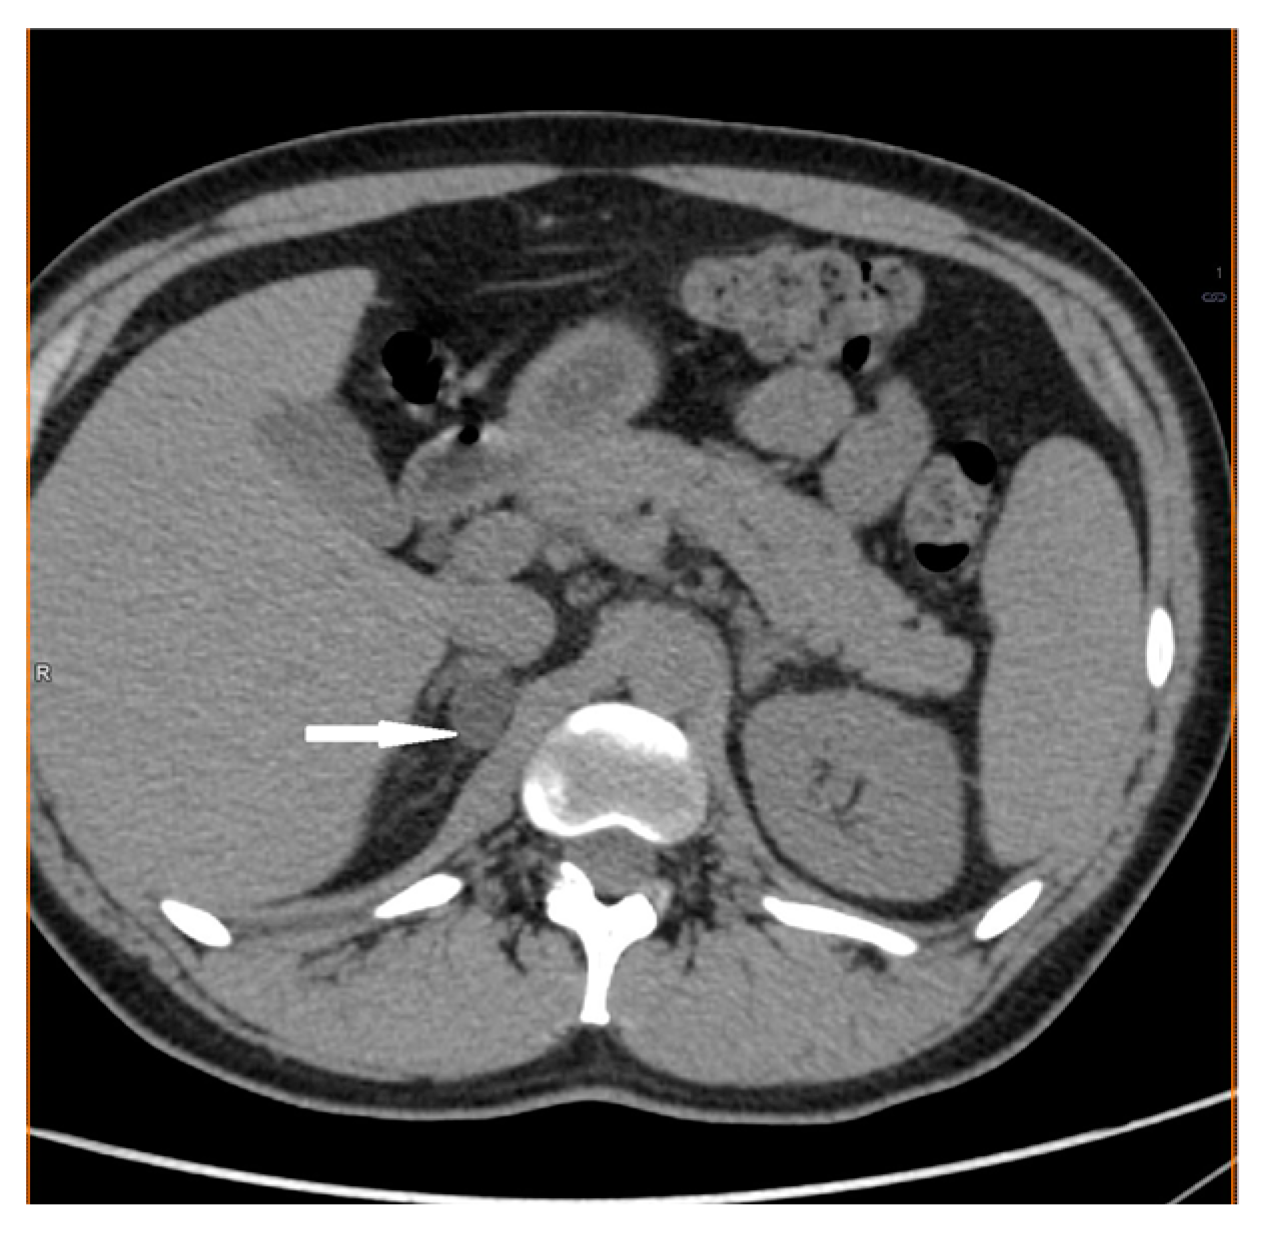

2.1. Case 1

2.2. Case 2

2.3. Case 3

2.4. Case 4

2.5. Case 5

2.6. Case 6

2.7. Case 7